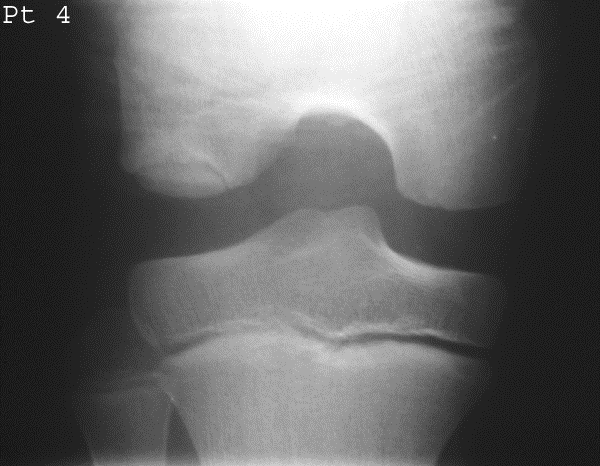

Most common site of Osteochondritis Dissecans?

Medial femoral condyle (75%).

How is it diagnosed radiographically?

MRI/CT for cartilage lesions; X-ray shows fragments and site of origin; tunnel view for knee.

What stage is this disease at?

Stage 4